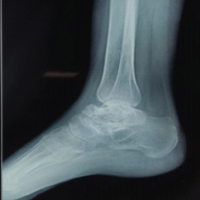

A 37-year-old male patient with hepatitis C presented with a persistent sinus tract at the surgical site following implant removal for an infected THA. The patient had undergone total hip replacement 4 years ago, which subsequently got infected. Implant removal was done 1 year back. Radiographs showing the left hip status after implant removal are shown in Fig. 1. At presentation, C-reactive protein (CRP), erythrocyte sedimentation rate (ESR), and total leukocyte count were 56 mg/L, 78 mm/h, and 14,700 cells/mm3, respectively. A two-stage revision was planned, and the risks and benefits were discussed with the patient.